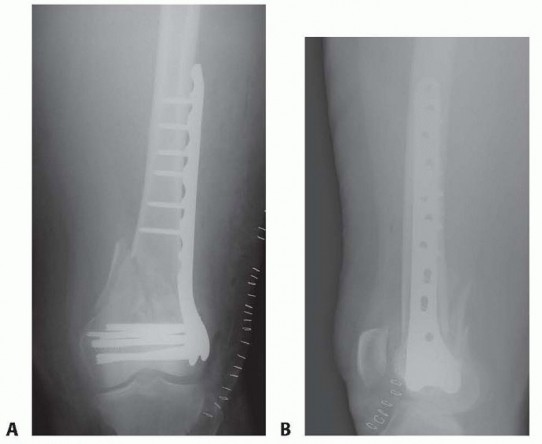

### FIG 11 • Morbidly obese female with a severely comminuted and open right distal C3 femur fracture. A,B. AP and lateral radiographs showing the amount of comminution, bone loss, and distal nature of the injury after the initial irrigation, débridement, and bridging external fixation. C,D. Intraoperative fluoroscopic images during application of a variable-angle locking plate. The AP shows the “central screw” to aid in reestablishment of the anatomic axis of the femur (parallel lines solid , screw; dashed , joint line). The lateral view shows the central screw, which is a fixed-angle hole (arrow and circle), as opposed to the variable-angle holes (red box ; both for the combination holes and isolated variable-angle screws). E,F. Two-week postoperative radiographs. The AP view shows the proximal screws placed perpendicular (dashed arrows) to the plate even through the variable-angle portion of the combination holes, which was facilitated by the targeting device. Both views demonstrate the advantage of the variable-angle locking holes distally to allow for additional fixation in this short distal segment with a more posterior and distal trajectory (solid arrows on lateral view). The bone substitute placed for the bone defect (white pellets) are also clearly visualized. (continued) 475

### FIG 11 • (continued) G,H. Five-month follow-up films showing replacement of the calcium sulfate beads with successful consolidation of the metaphyseal comminution. The flexibility of fixation constructs can be increased by the use of a technique referred to as far cortical locking. Specialized screws are used, in which the screw locks into the plate and only engages the far cortex. This has been thought to improve fracture healing. 5 The “polyaxial” locking plates have been shown to be biomechanically sound in the management of supracondylar femur fractures. 12, 18 ## Preoperative Planning Surgical timing can be affected by the following: Soft tissue issues Medical condition of the patient Adequacy of available operative team Availability of implants The approach must take the following issues into consideration: The ability to incorporate lacerations in open fractures into the incision ( FIG 13) can be useful and should be considered. However, this is not always necessary or possible.